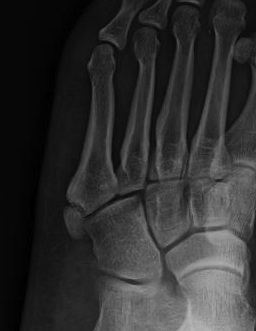

Base of 5th - Zone 1 / 2 / 3

Base Shaft Neck

![]() |

| Incidence: 93% | 4% | 3% |

Dean et al Foot Ankle Spec 2012